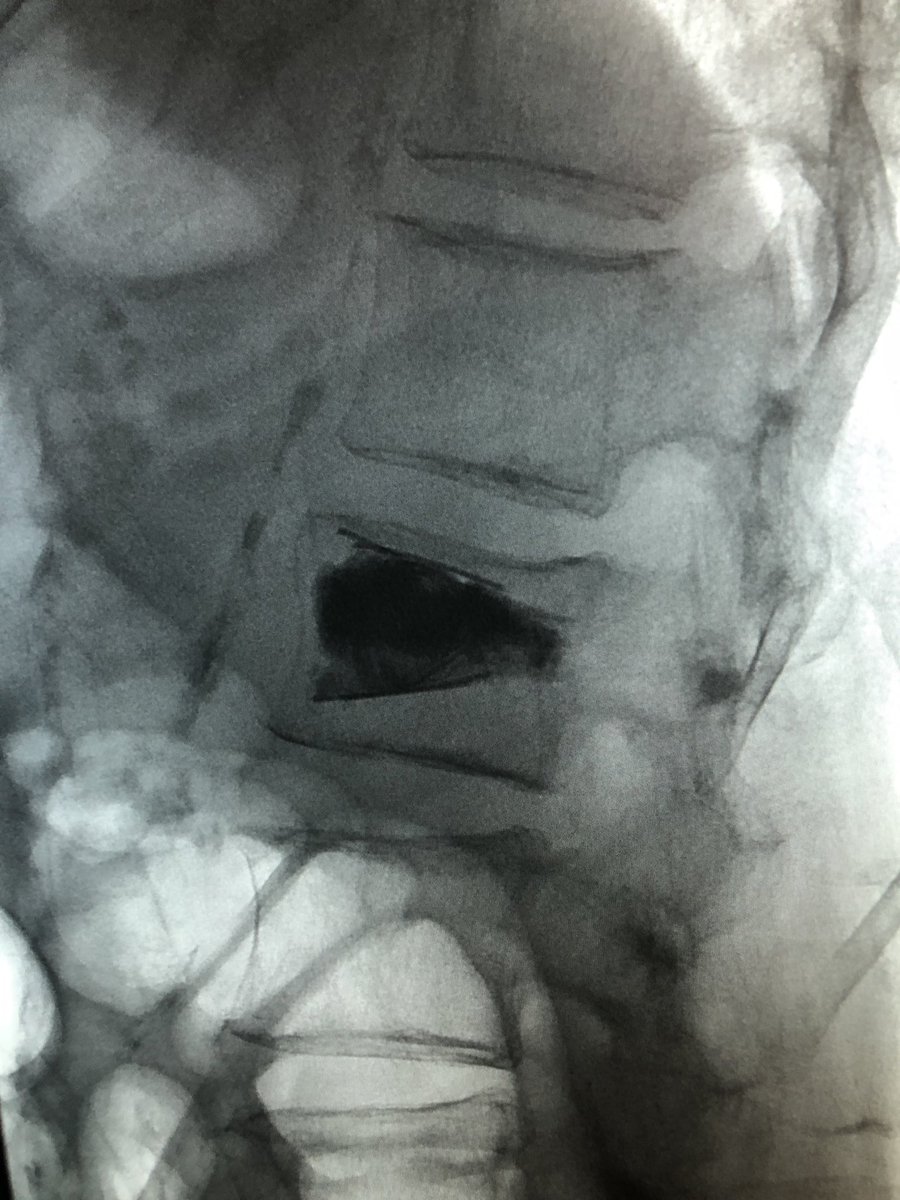

#IRad#SpineRad#NeuroRad: Neurogenic claudication due to Synovial cyst, completely resolved after cyst rupture. Probably, one of the easiest procedures in Radiology with tremendous benefit to patients. pic.twitter.com/gOYqHnqK8r